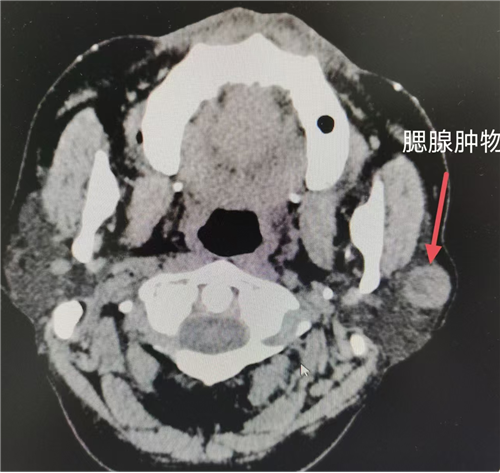

目前腮腺区肿瘤手术方式多为腮腺肿物切除 + 腮腺腺叶切除 + 面神经解剖(若术后病理提示恶性肿瘤,需联合放化疗)。术前需完善腮腺区彩超及颌面部影像学检查,必要时加做颌面部增强 MRI 检查,以明确病变范围、肿物大小、性质以及与周围组织解剖学关系。